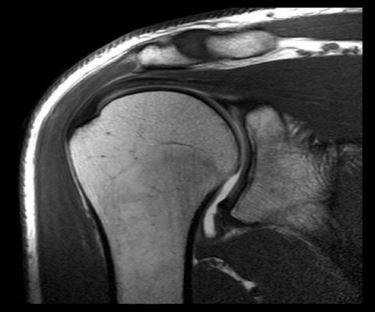

Диагностика вывиха на снимках МРТ и КТ плечевого сустава

Причины: обычно травматический, менее часто привычный (при слабости капсулы плечевого сустава).

Типы вывиха

Передний вывих (97%): обычно связан с непрямым приложением силы; сочетание разгибания, супинация и отведения.

Задний вывих (2-3%): обычно связан с непрямым приложением силы; сгибание, пронация и приведение, например при повреждении электрическим током или эпилептическом припадке.

Редкие типы: вывих с расхождением крыши плечевого сустава; нижний вывих (выпрямленный вывих).

Какой метод диагностики вывиха плеча выбрать: МРТ, КТ, рентген

Метод выбора

Что покажут рентгеновские снимки при вывихе плеча

- Рентгенологическое исследование в двух проекциях: прямая тангенциальная (касательная) проекция суставной полости и чрезлопаточная проекция.

Передний вывих: головка плечевой кости расположена кпереди и книзу, обычно ниже клювовидного отростка; в редких случаях она может находиться на нижней границе суставной полости.

Задний вывих: головка плечевой кости перекрывает границу суставной полости; суставная щель не визуализируется.

Частые сопутствующие повреждения

- Отрыв большого бугорка

- Повреждение Хилла-Сакса: передний вывих с дефектом кости на заднелатеральной поверхности головки плечевой кости; соответствует месту, где головка плечевой кости находит на нижнюю границу суставной полости; возможно изображение в прямой проекции с пронацией плеча.

- Реверсный дефект Хилла - Сакса: возникает при заднем вывихе плечевого сустава; рядом с поврежденным бугорком плечевой кости.

- Повреждение Банкарта: дефект хрящевой ткани и/или кости на нижней границе

суставной полости/суставной губы.

a,b Передний вывих плечевого сустава у женщины 46 лет после падения на вытянутую руку. (а) Рентгенологическое исследование праовго плечевого сустава в прямой проекции с ротацией противоположной стороны туловища на 40° кпереди и на (b) Y-проекция. Суставная впадина пуста. Передненижнее смещение головки плечевой кости ниже клювовидного отростка.

а, b Задний вывих плечевого сустава у женщины 45 лет после падения с велосипеда, (а) Рентгенологическое исследование правого плечевого сустава. Суставная щель в прямой проекции не визуализируется, плечо ротировано медиально.(b) Y-проекция четко демонстрирует задний вывих.